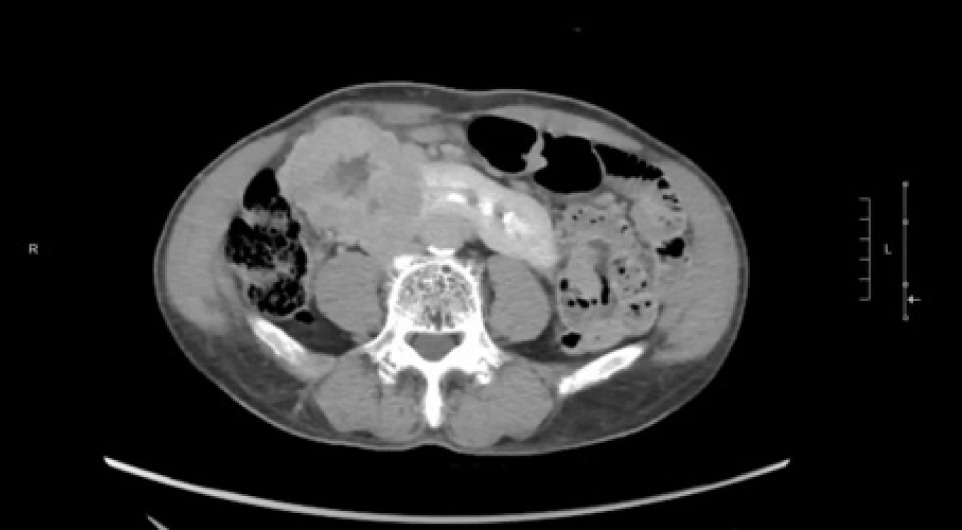

A 74-year-old Chinese male patient, ex-smoker, and social drinker, with a history of carcinoma of prostate in remission with laparoscopic radical prostatectomy done 11 years ago presented with an incidental finding of a right abdominal mass without frank symptoms. Preoperative eGFR ranges from 80 to 90 mL/min/1.73m2. Computed tomography (CT) showed a 7 cm heterogeneous mass on the right side of the HSK with complex hilar anatomy (Figures 1 & 2). Dual tracer (C-11 acetate and F18 FDG) positron emission tomography (PET-CT) showed moderate and mildly avid renal cell carcinoma (RCC) arising from HSK, without nodal or distant metastases. A 3D image reconstruction using FUJIFILM Synapse system was performed, showing complex tumor and vascular anatomy (two renal arteries and an additional artery to isthmus) (Figure 3). An open partial right nephrectomy was planned.

Figure 2: Axial cut of delayed phase-enhanced CT abdomen at the tumor level.